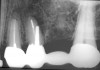

The length of the post space should be at least one half the root length while still maintaining the apical seal of gutta-percha.3,7,37 It is recommended that gutta-percha be removed using a heated endodontic instrument and/or canal-safe Gates-Glidden drills. Aggressive use of inflexible post drills within the root canal can lead to perforation of the canal with subsequent negative consequences on the survivability of the tooth (Figure 2).3,7 This author recommends that the post drills provided by manufacturers be used more as a canal-sizing instrument than for post preparation within the canal. The rationale for using the post drill in this manner assures that the root canal is not overprepared with the potential of perforation of the root canal. It is important when removing the gutta-percha that the length of the root canal be known so that whichever technique is used to remove the gutta-percha, the instrument can be marked to the length of root canal preparation desired. In the case of a rotary instrument or a heated instrument, an endodontic stopper can be placed on the instrument to the length desired (Figure 3). After making the post space, it is advisable to make a radiograph of that tooth to verify the length of the post space and the removal of the gutta-percha (Figure 4).

Figure 4  Take verifying radiographs to check on gutta- percha removal and length of post space desired.

Figure 4